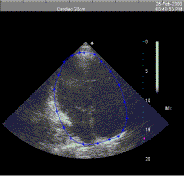

Figure 2. Typical apical four-chamber ultrasound image with points on the heart surface and cubic spline contour generated from the points.

Our cardiac probe was calibrated as described above, and images of a normal adult subject were obtained in multiple views. A typical apical four-chamber view is shown in Figure 2, with points overlaid that we identified as part of the heart surface. Analysis was performed with a side-by-side comparison of the static image shown here and a loop of images showing the cardiac cycle. This image was chosen at end-diastole as judged by visual inspection of motion in the image loop. For this subject, ten images were acquired, consisting of apical two- and four-chamber images, and parasternal long- and short-axis images at multiple view angles in an attempt to maximize coverage of the heart surface. The image planes are shown in Figure 3, in roughly the same orientation as the heart and torso surface shown in Figure 4. The heart surface points identified on each image are also plotted. The convex hull of the heart surface points shown in Figure 3 was generated to form a closed, triangulated surface. That surface is shown in Figure 4 inside a semi-transparent model of the subject’s torso. Relative alignment of the two surfaces was known in this case based on identification of homologous points in the torso model and on the subject during data collection. In general, all torso and heart points would be acquired relative to the same reference coordinates.